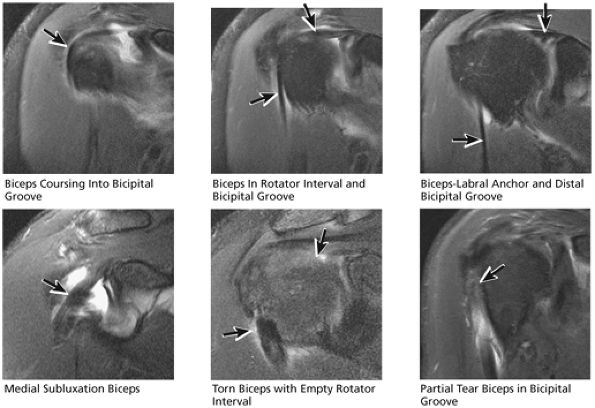

FIGURE 8.34 Biceps Tendon.